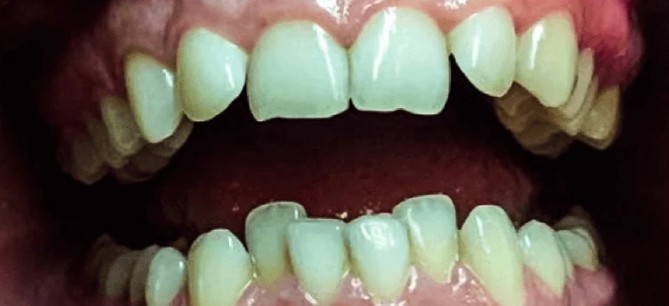

У пациента было глубокое перекрытие резцов, тремы верхнего зубного ряда (щели), протрузия верхних резцов (выступания). Лечение с помощью сапфировой брекет-системы 12 месяцев.

Доктор: Хачатрян Лариса Рубеновна